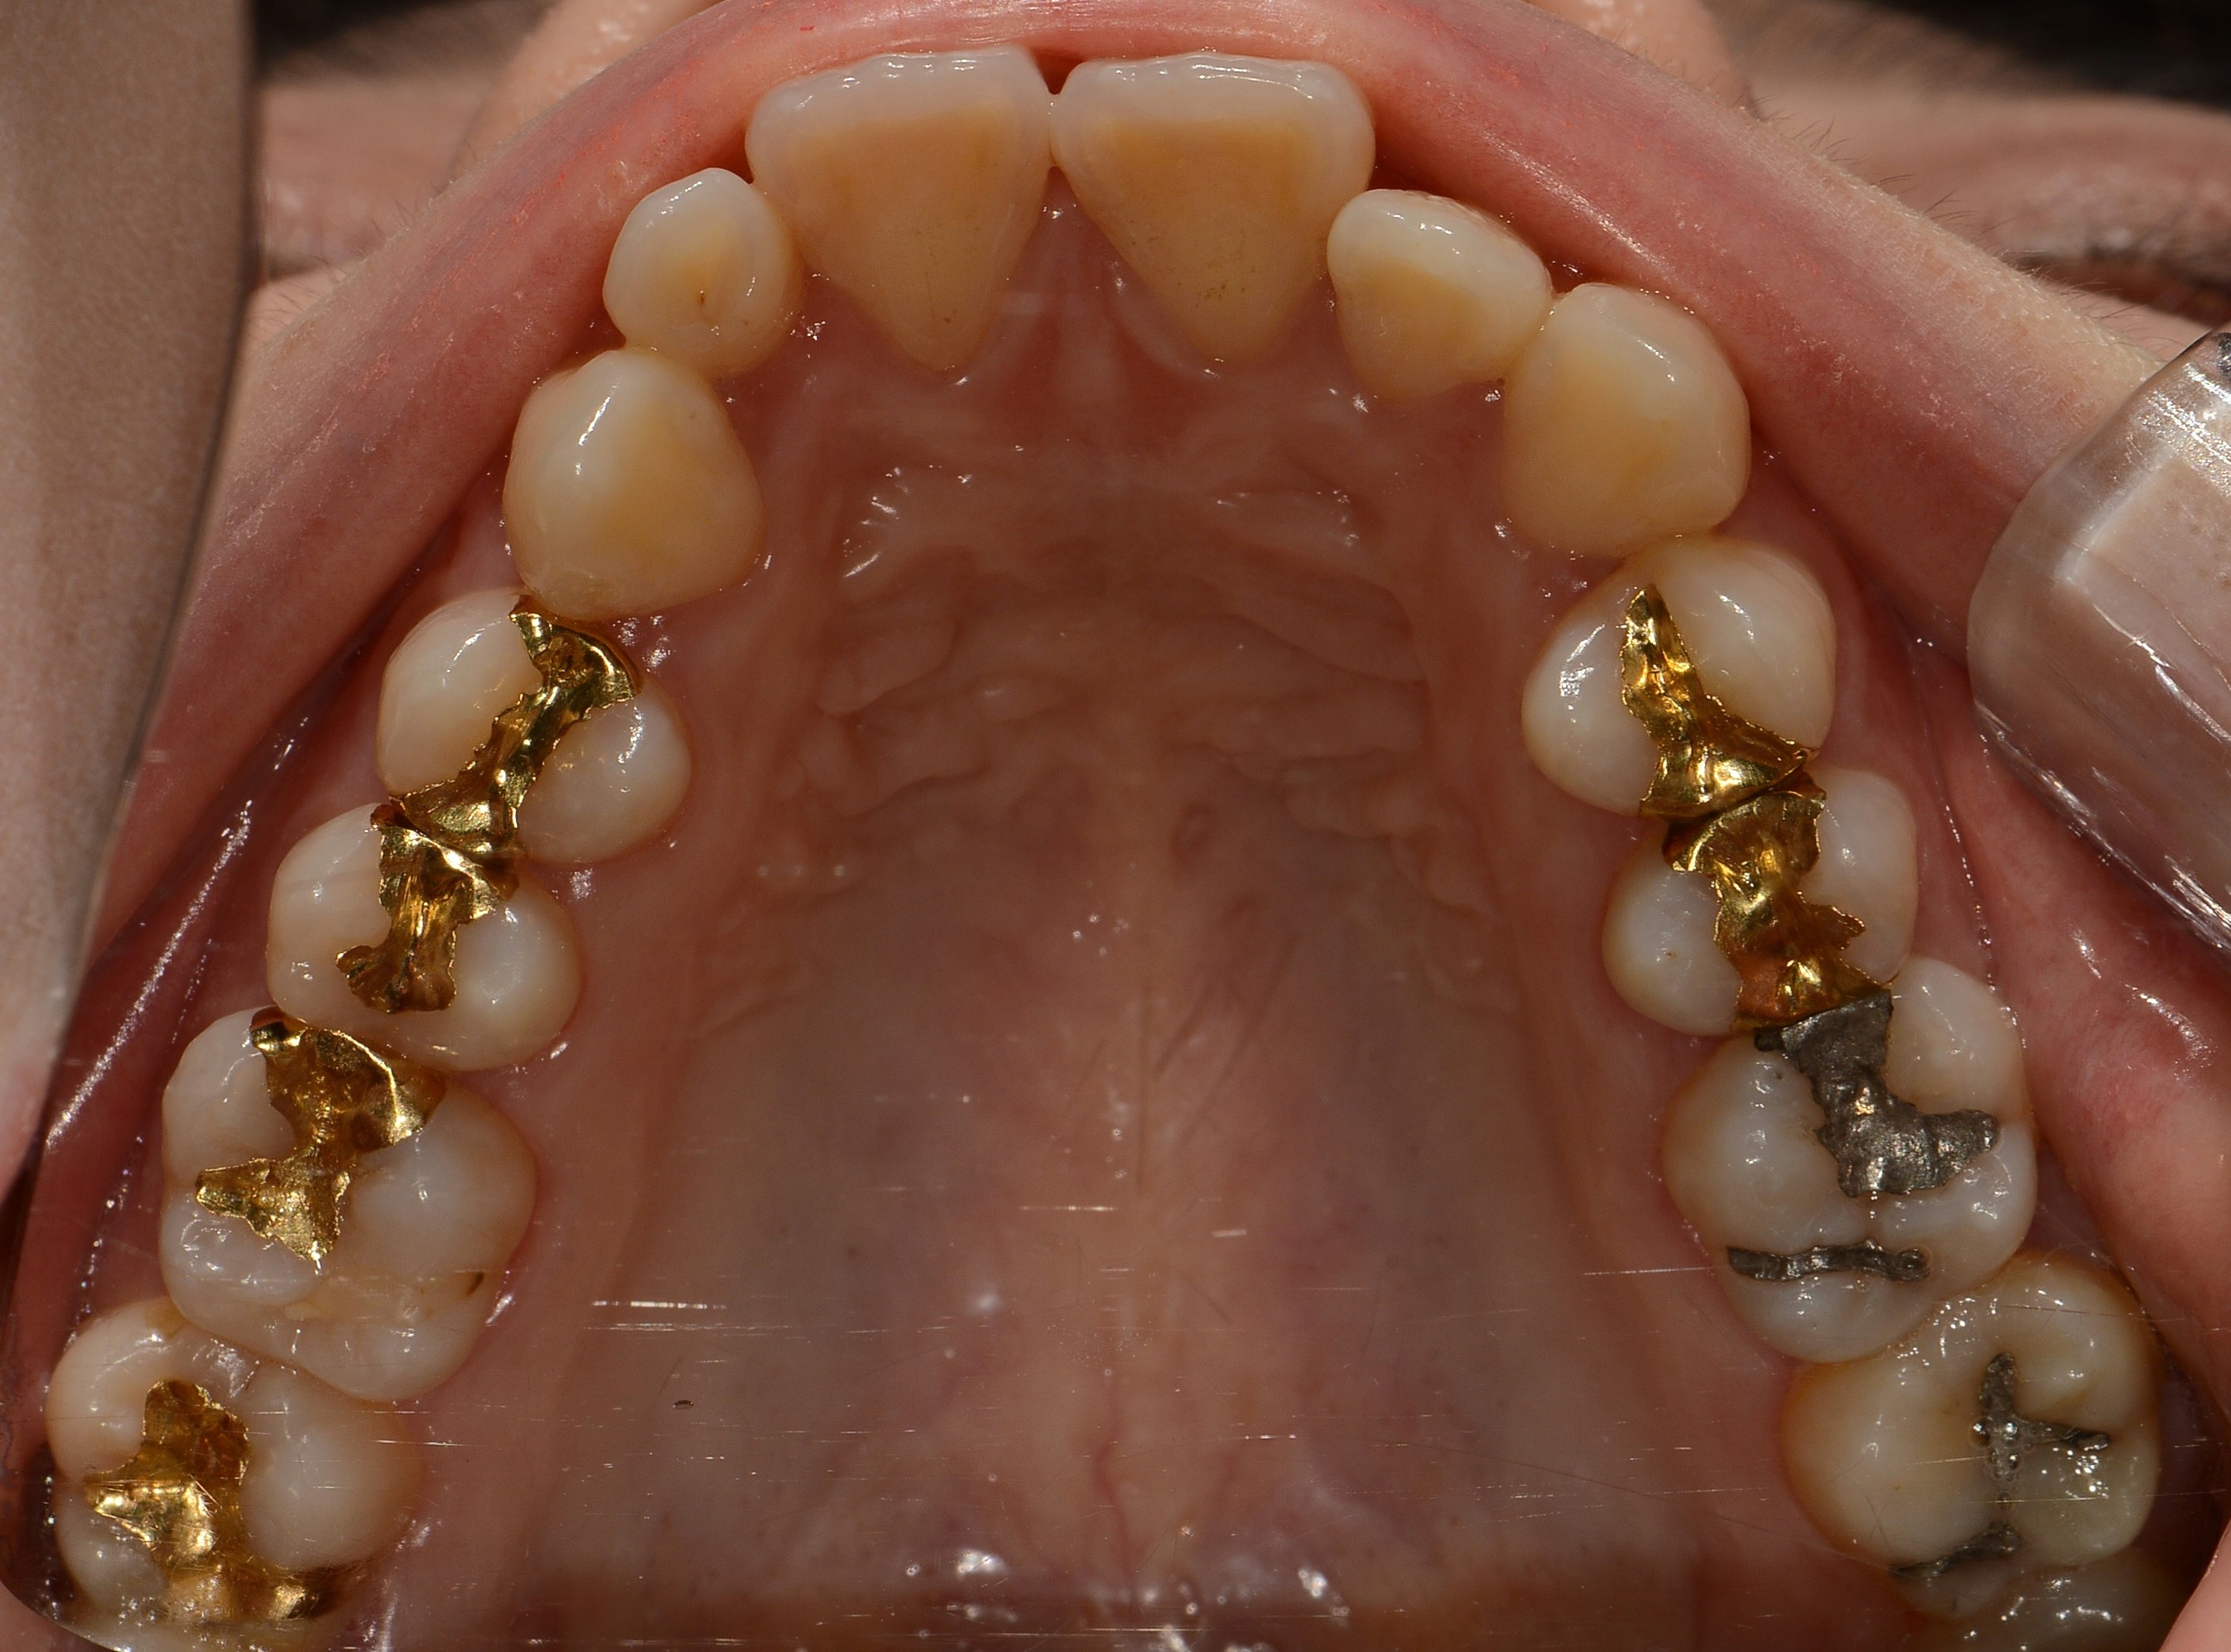

치료 전 사진입니다.